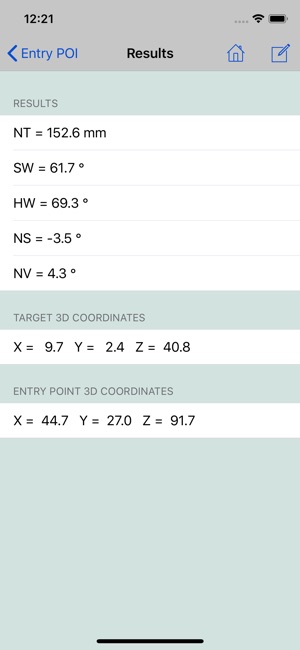

10.At this point the stereotactic parameters NT, SW, HW, NS and NV will be computed and displayed.

If you want to keep a copy of results for your records, use the Compose button on top of the screen to send them by e-mail.